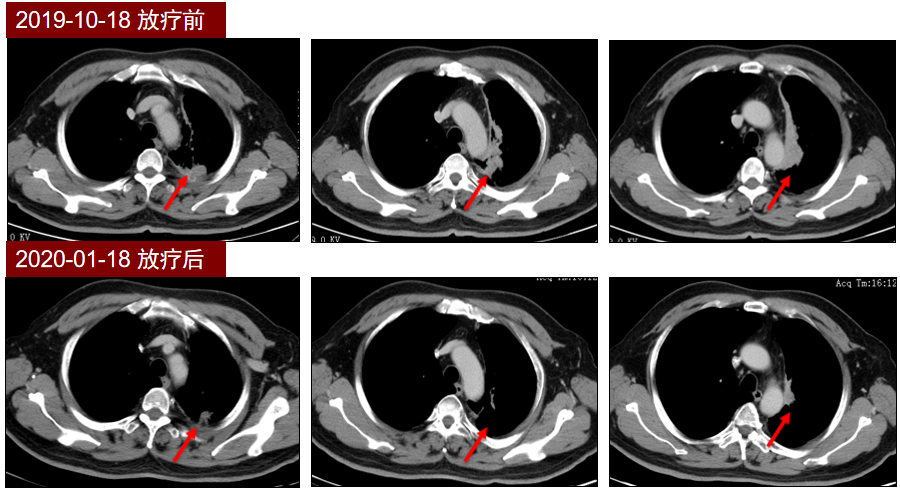

本期分享一例TNM分期为IIIB期的不可切除局部晚期NSCLC患者,初始采用重组人血管内皮抑制素联合同步放化疗进行治疗,然后以重组人血管内皮抑制素联合PD-L1单抗巩固治疗,患者初始治疗达到部分缓解(PR),同步放化疗后巩固治疗阶段病情稳定(SD),累计无进展生存期(PFS)已接近12个月。

结合患者分期及驱动基因检测阴性,经全院MDT会诊后,2019年11月开始行重组人血管内皮抑制素静脉持续泵入治疗(15mg/d),并联合培美曲塞+顺铂化疗及影像引导放疗(IGRT,剂量为60-66Gy/30-33/6-7周)2个周期,疗效评价PR,转入巩固治疗阶段。治疗期间患者曾出现白细胞减少、血小板减少、疲乏等不良事件,最高为3级(白细胞减少),重组人粒细胞集落刺激因子(rhG-CSF)支持治疗后缓解,其它不良事件均为1-2级。

2020年3月,患者开始使用重组人血管内皮抑制素持续泵入(30mg/d,D1-7),联合PD-L1抑制剂度伐利尤单抗(Durvalumab)联合行巩固治疗,治疗3月后复查,疗效评价SD,持续原方案巩固治疗至今,最近一次复查疗效评价仍为SD。

本例IIIB期患者起始治疗应用重组人血管内皮抑制素联合同步放化疗,实现肿瘤部分缓解,巩固治疗阶段应用了重组人血管内皮抑制素联合 PD-L1抑制剂度伐利尤单抗,达到较好的疾病控制效果,目前PFS已接近12个月,疗效已超过传统同步放化疗阶段的中位PFS,有望接近PACIFIC研究中度伐利尤单抗治疗组17.2个月的中位PFS[1]。